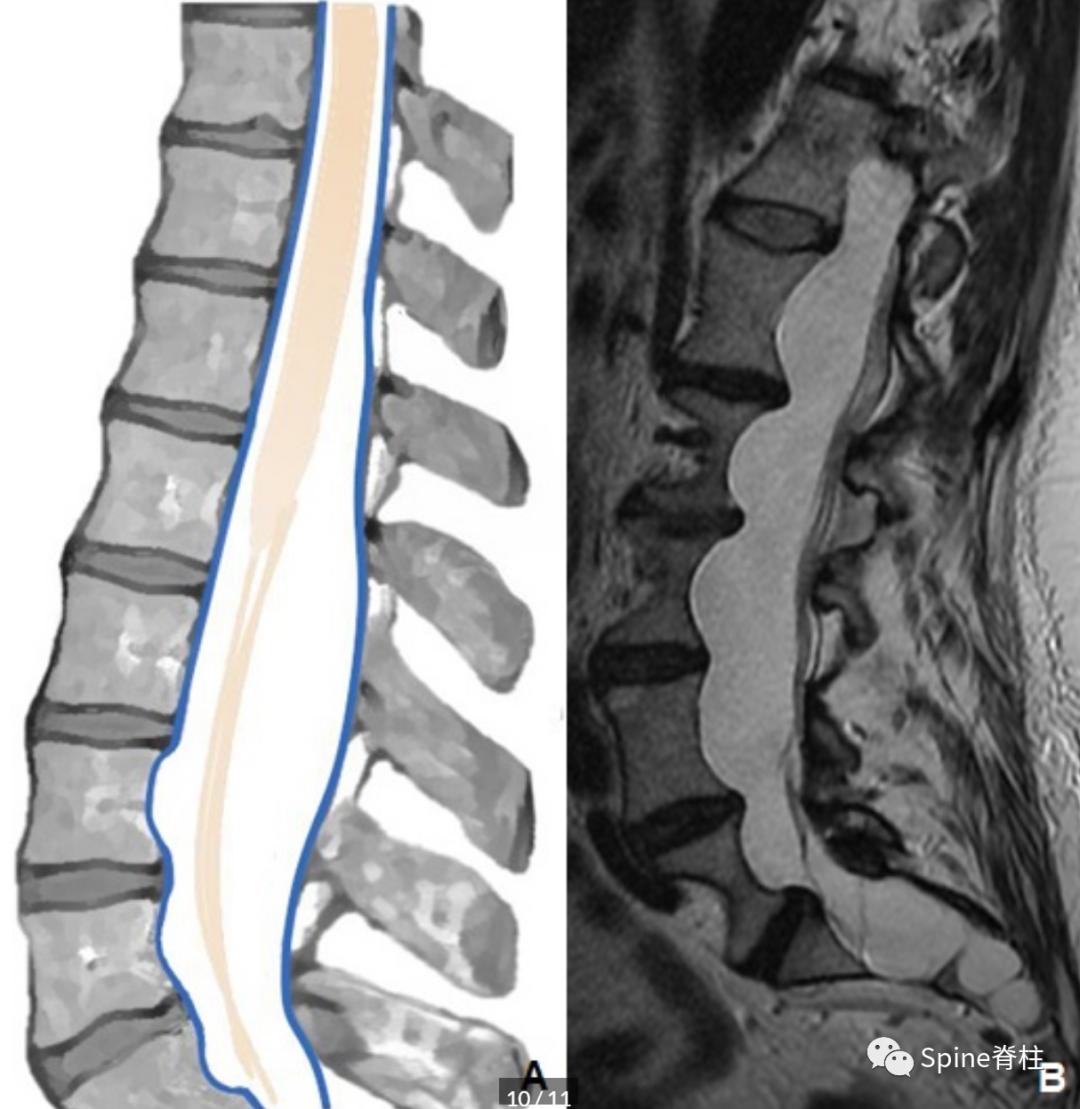

3. 硬膜扩张 (III 型)

硬膜梭形扩张主要见于影响结缔组织疾病如马凡综合征患者的腰骶段。这种表现也可能是强直性脊柱炎和Ⅰ型神经纤维瘤病的特征性表现,可能涉及整个硬膜或个别神经根袖。与硬膜内外层之间的囊肿(II型)类似,硬膜扩张也可导致低压综合征,尤其是马凡综合征患者。MRI上, 硬膜扩张很容易就可识别(下图)。

一名47岁的马凡综合征患者。模式图提示硬膜扩张的典型表现。矢状位T2加权像提示腰骶部硬膜扩张,脊髓圆锥粘附于硬膜后部(B)